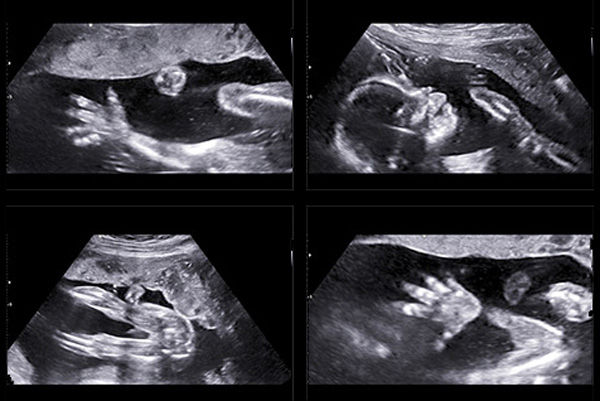

سونوگرافی حاملگی یکی از روشهای تصویربرداری است که برای بررسی وضعیت جنین و سلامت مادر در دوران بارداری استفاده میشود. این روش به کمک امواج صوتی، تصاویری از جنین، جفت، و مایعات آمنیوتیک تولید میکند. سونوگرافی در طول بارداری میتواند به تشخیص مشکلات احتمالی و نظارت بر رشد و توسعه جنین کمک کند. در ادامه به جزئیات بیشتری درباره شرایط سونوگرافی حاملگی پرداخته میشود.

سونوگرافیهای ۳ بعدی و ۴ بعدی: این نوع سونوگرافیها به تصویرسازی بهتر جنین و مشاهده حرکات آن کمک میکنند.

تمام بررسی های آناتومیک نوزادان متولد نشده در سیستم بیمارستان های دانشگاهی توسط متخصصان سونولوژیست آموزش دیده انجام می شود. اینها پزشکانی هستند که متخصص سونوگرافی هستند و از تصویربرداری سه بعدی و چهار بعدی با وضوح بالا برای مشاهده دقیق ترین جنین استفاده می کنند. این پزشک بسیار ماهر و با تجربه، که می داند به دنبال چه چیزی باشد، سونوگرافی را ارزیابی می کند. سونوگرافی های اضافی توسط سونوگرافیست ها انجام می شود – تکنسین هایی که در تصویربرداری اولتراسوند OB تخصص دارند و توسط یک تیم مجرب از متخصصان ژنتیک بالینی کودکان آموزش دیده اند.

آزمایشات و مراحل پیشرفته جنین